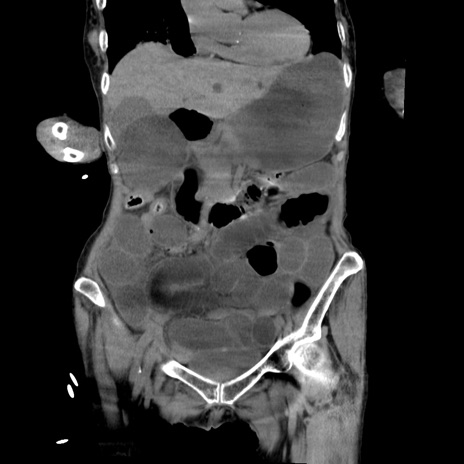

症例27(冠状断像)

【症例】80歳代女性

【主訴】嘔吐、腹痛

【現病歴】数時間前より嘔吐あり。心窩部痛出現し、徐々に右下腹痛あり。その後も数回嘔吐あり救急搬送となる。

【既往歴】左大腿骨頚部骨折手術

【身体所見】腹部は膨隆しているが軟らかく圧痛なし。腸雑音はやや亢進。

【データ】WBC 12000、CRP 19.05